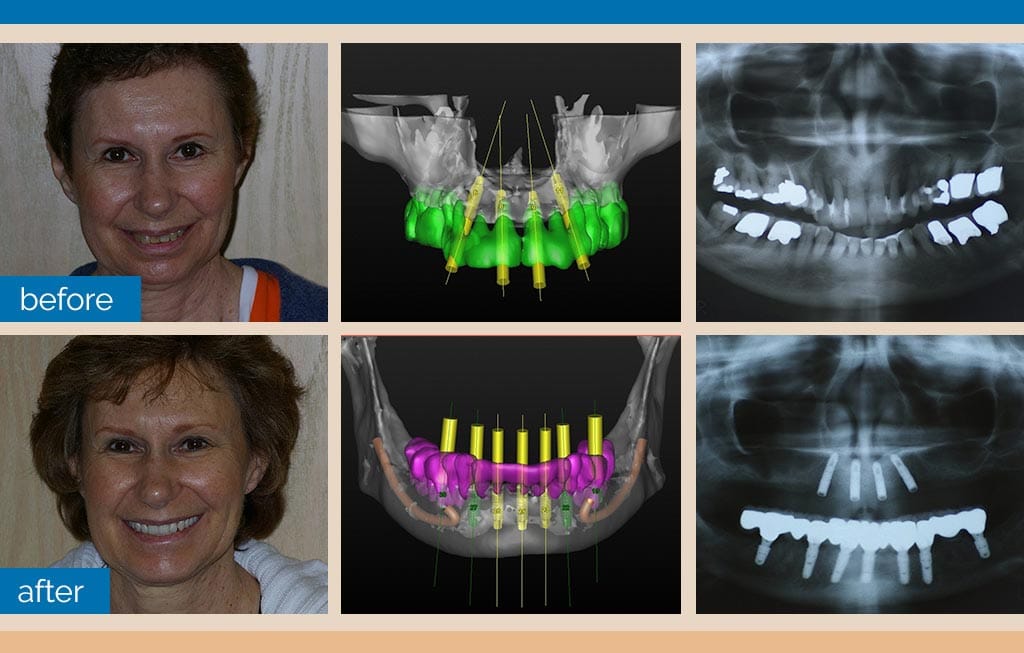

Up until just a few years ago, implant dentistry diagnostics and treatment planning used conventional X-rays and panographs for assessing bone and tissue quantity and quality, along with basic 2D technical data used for determining where each implant would be placed. Conventional X-rays, however, oftentimes failed to reveal certain tissue conditions that could contribute to or directly cause an unwanted tooth implant failure.

These “conditions” wouldn’t be revealed until dental implant surgery actually began. These normal events of “undiscovered diagnostic data” were routinely blamed for sudden changes in treatment planning or, in other cases, where seemingly successful dental implants failed after treatment was completed.

In our office, and many of Dr. Nazarian’s training seminars, the Carestream 81003D Scanner is used to fully assess all bone and soft tissue within the oral cavity. The ability to rotate and view all tissue from all possible perspectives assures that ALL tissues are assessed accurately, regardless of how hidden they may be.

Dr. Nazarian’s use of 3D imaging reveals all tissue characteristics and, when used in conjunction with specialized scanning software, enables the patient and Dr. Nazarian to develop the ideal surgery protocols for placing a single tooth implant, several implants, or an entire arch of teeth.

A patient’s entire dental implant surgery protocol is planned and visualized before treatment even begins. The 3D scanning software is used to create special surgical templates for preparing bone tissue (where it needs to be trimmed or revised) and for creating a surgical guide that assures each and every implant is placed at a precise location with precise depth, width, and centering within the jawbone. Errors are virtually eliminated.

Each and every tooth implant is selected and placed based on the technical data provided by the scan. Different dental implant types, widths, and lengths are individually selected for each location. The concept of one-dental-implant-fits-all no longer exists.